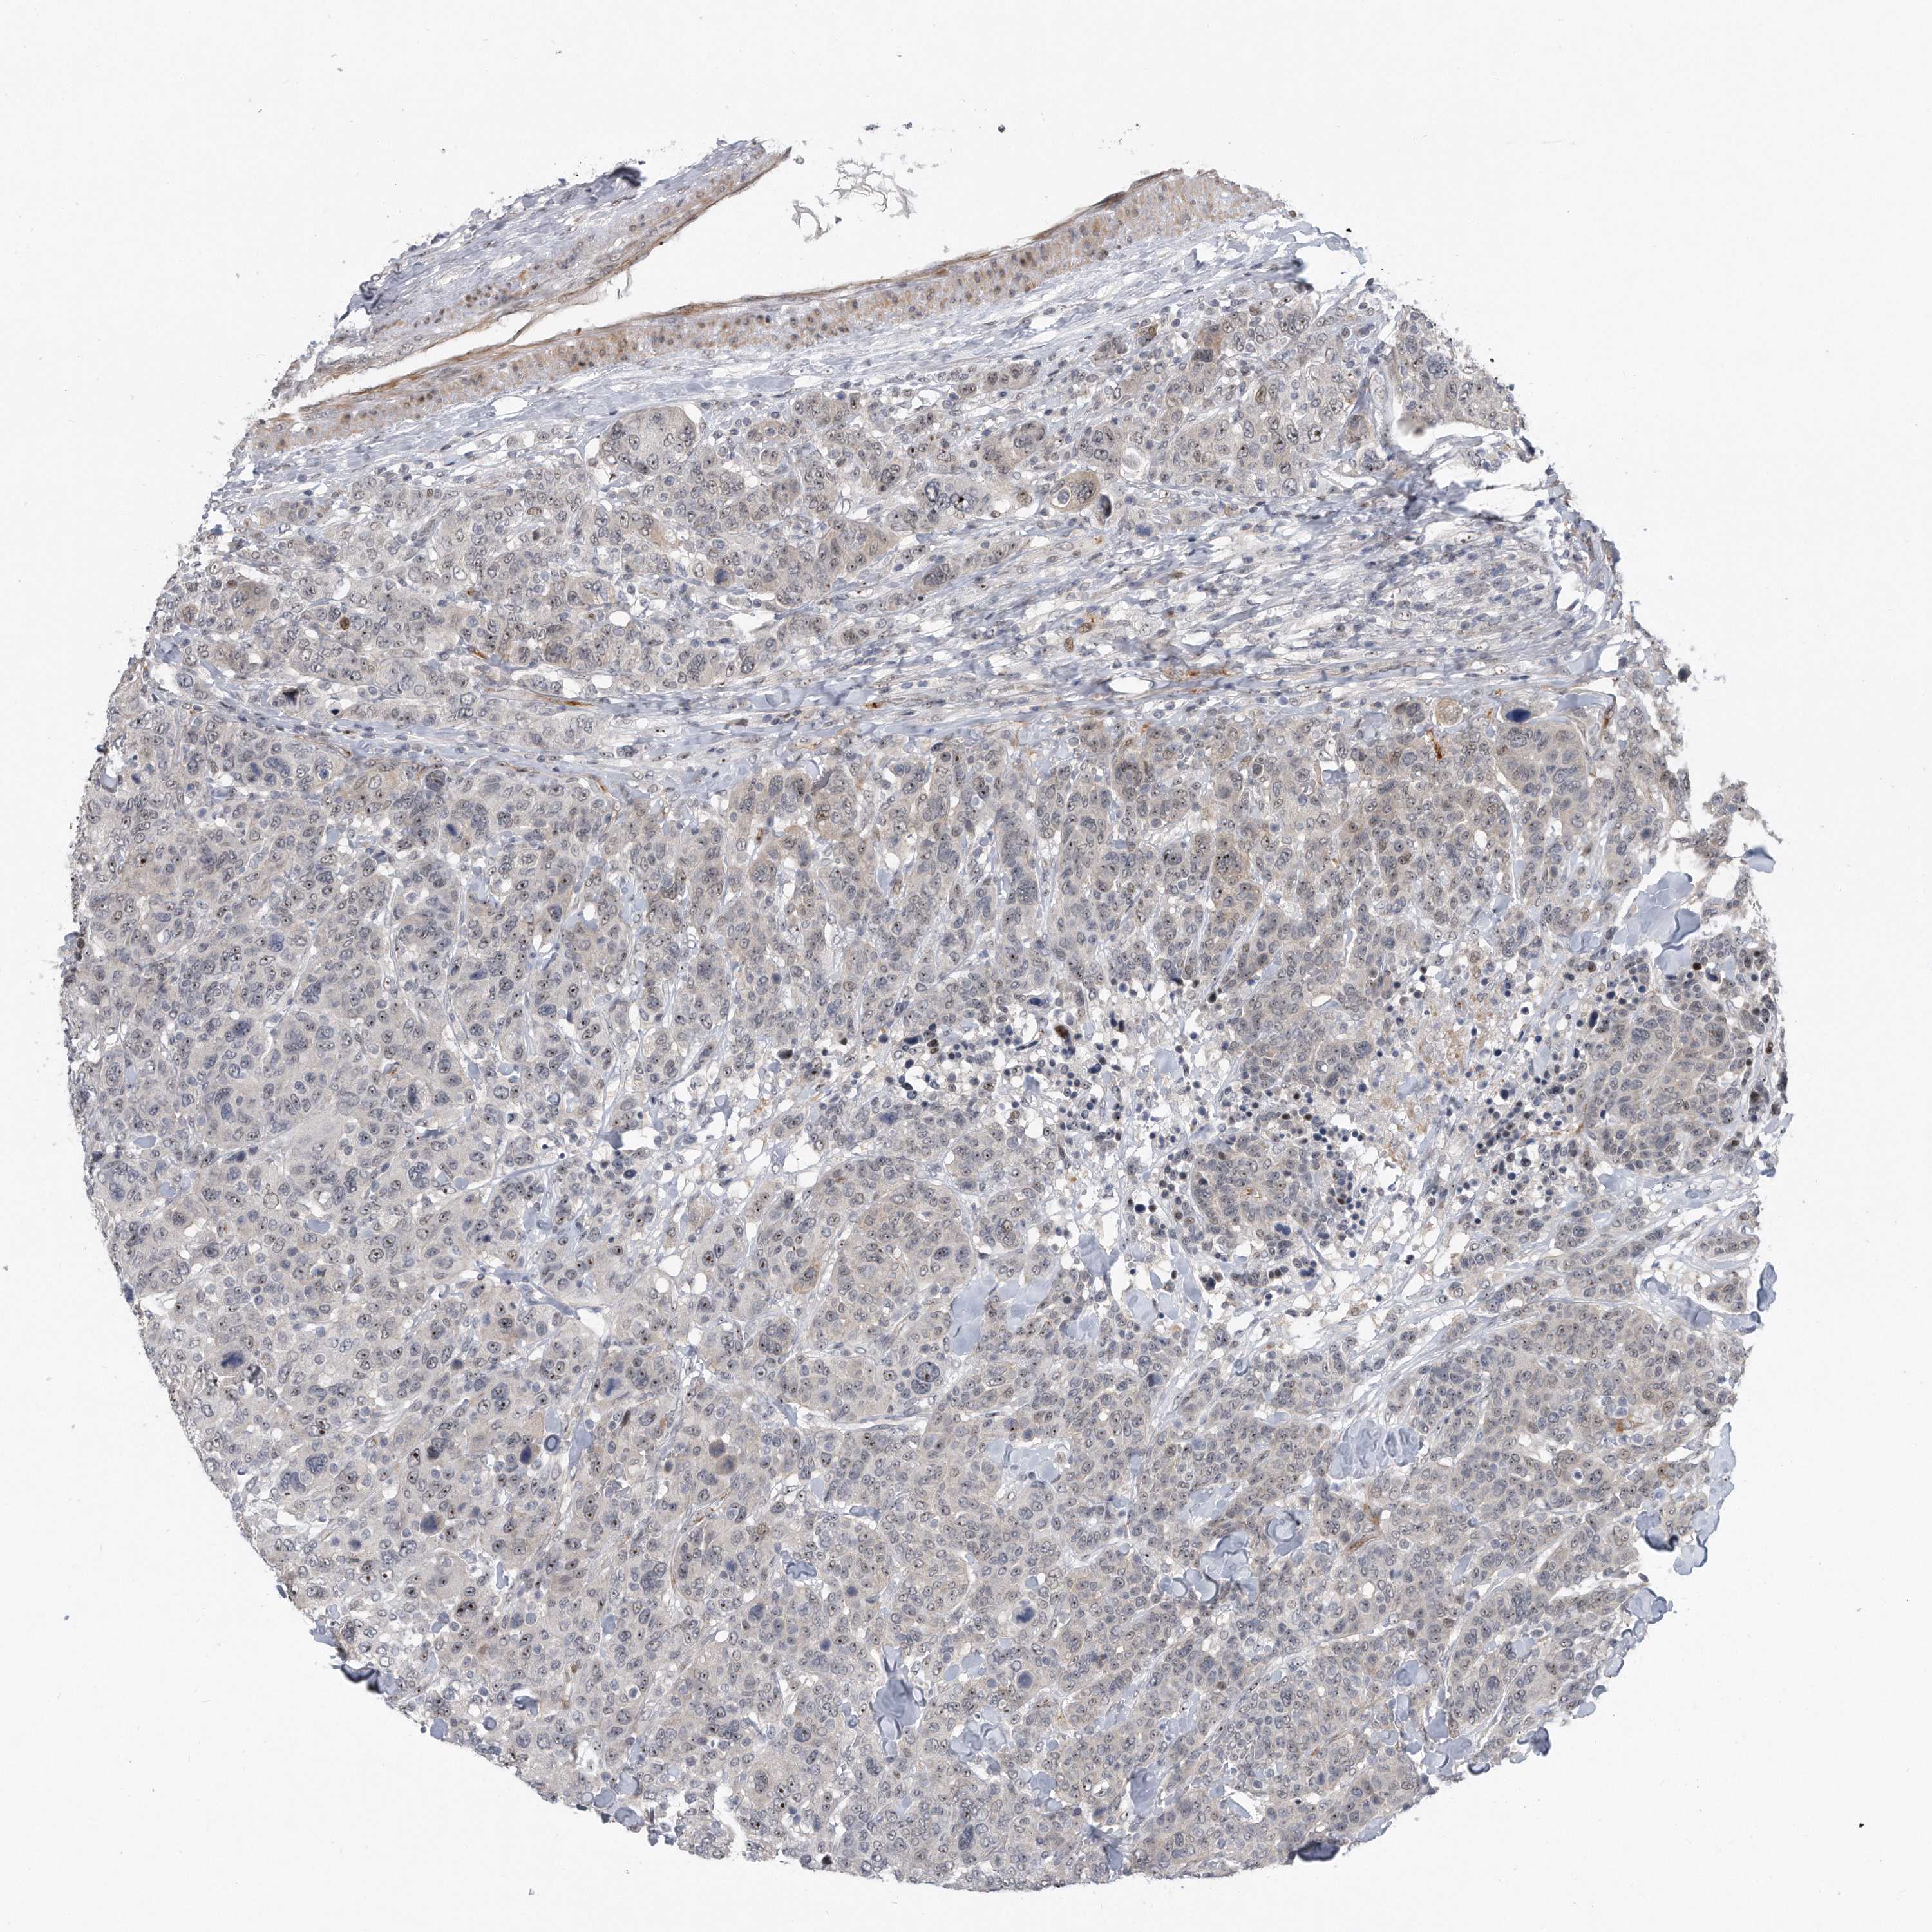

CANCER BREAST CANCER Show tissue menu

BRCA TCGA BRCA VALIDATION PROTEIN EXPRESSION

ANTIBODIES

AND

VALIDATION